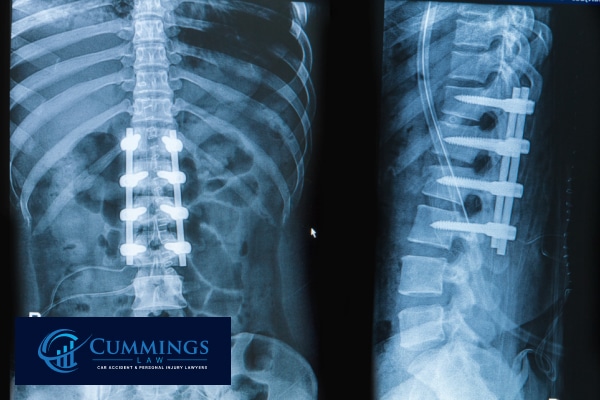

Spinal injuries may lead to partial or complete paralysis. Victims often need ongoing therapy and adaptive equipment to regain movement. The medical expenses for spinal cord injuries are among the highest in personal injury cases.